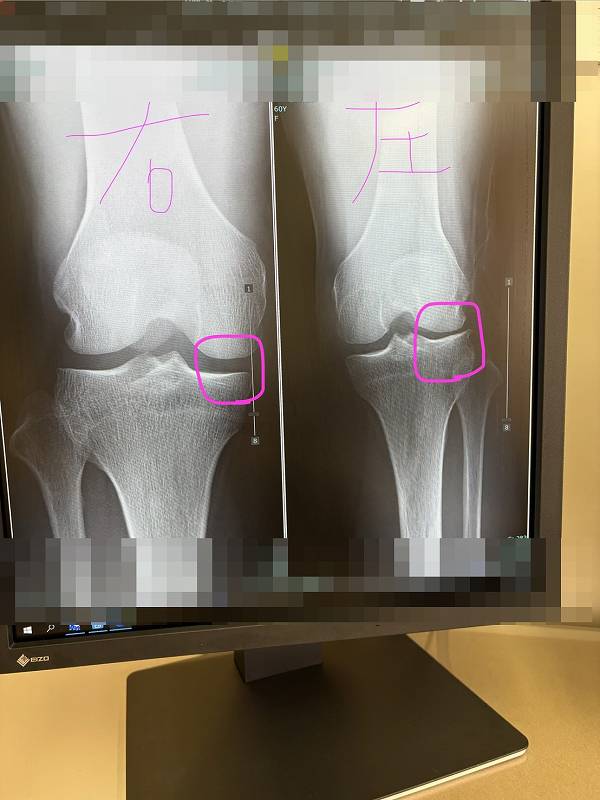

スネの骨が外に回った状態のまま

レントゲンを撮れば、

膝の外側の関節の隙間は狭く写ります。

反対に、

スネが内側に回った状態で撮影すれば、

内側の関節の隙間が狭く写ります。

つまり、

レントゲンに写る「隙間」は、

関節の向きによっても変わるということです。